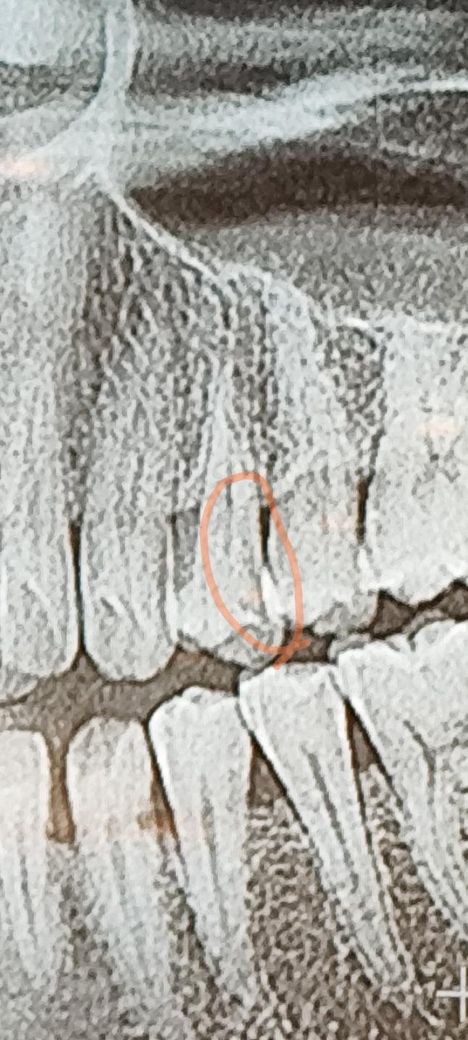

셀프치석제거기로 욱신욱신 수시는 부위가 있어서 잇몸뿌리부분 거기를 조금깊게 치석제거기로 긁엇더니 검을 물인지 고름인지같은게 치아에서 막나와요 이거 충치 고름인가요?

갈아낸 부분은 엑스레이 사진상 동구라미친 부위에

뿌리부분이에요

치아의 밑면부분은 레진치료를 받앗는데. 윗부분은 의사가 발견을 못한건지 치료를 안한거 같아요 치료받아야 하나요?